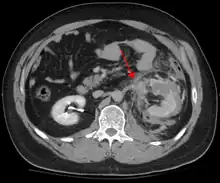

Blunt abdominal trauma (BAT) represents 75% of all blunt trauma and is the most common example of this injury.[3] 75% of BAT occurs in motor vehicle crashes,[4] in which rapid deceleration may propel the driver into the steering wheel, dashboard, or seatbelt,[5] causing contusions in less serious cases, or rupture of internal organs from briefly increased intraluminal pressure in the more serious, depending on the force applied. Initially, there may be few indications that serious internal abdominal injury has occurred, making assessment more challenging and requiring a high degree of clinical suspicion.[6]

When blunt abdominal trauma is complicated by 'internal injury,' the liver and spleen (see blunt splenic trauma) are most frequently involved, followed by the small intestine.[8]

In most settings, the initial evaluation and stabilization of traumatic injury follows the same general principles of identifying and treating immediately life-threatening injuries. In the US, the American College of Surgeons publishes the Advanced Trauma Life Support guidelines, which provide a step-by-step approach to the initial assessment, stabilization, diagnostic reasoning, and treatment of traumatic injuries that codifies this general principle.[8] The assessment typically begins by ensuring that the subject's airway is open and competent, that breathing is unlabored, and that circulation—i.e. pulses that can be felt—is present. This is sometimes described as the "A, B, C's"—Airway, Breathing, and Circulation—and is the first step in any resuscitation or triage. Then, the history of the accident or injury is amplified with any medical, dietary (timing of last oral intake) and history, from whatever sources such as family, friends, previous treating physicians that might be available. This method is sometimes given the mnemonic "SAMPLE". The amount of time spent on diagnosis should be minimized and expedited by a combination of clinical assessment and appropriate use of technology,[33] such as diagnostic peritoneal lavage (DPL), or bedside ultrasound examination (FAST)[34] before proceeding to laparotomy if required. If time and the patient's stability permits, CT examination may be carried out if available.[35] Its advantages include superior definition of the injury, leading to grading of the injury and sometimes the confidence to avoid or postpone surgery. Its disadvantages include the time taken to acquire images, although this gets shorter with each generation of scanners, and the removal of the patient from the immediate view of the emergency or surgical staff. Many providers use the aid of an algorithm such as the ATLS guidelines to determine which images to obtain following the initial assessment. These algorithms take into account the mechanism of injury, physical examination, and patient's vital signs to determine whether patients should have imaging or proceed directly to surgery.[8]